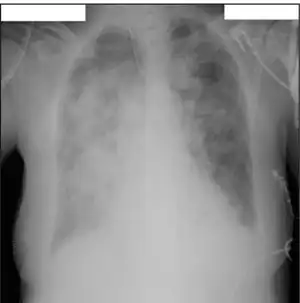

Acute respiratory distress syndrome primary caused by influenza B virus infection

In 1940, an acute respiratory illness outbreak in Northern America led to the discovery of influenza B virus (IBV), which was later discovered to not have any antigenic cross-reactivity with influenza A virus (IAV). Based on calculations of the rate of amino acid substitutions in HA proteins, it was estimated that IBV and IAV diverged from one another around 4000 years ago.[32] However, the mechanisms of replication and transcription, as well as the functionality of the majority of viral proteins, appear to be largely conserved, with some unusual differences.[33] Although IBV has occasionally been found in seals and pigs, its primary host species is the human.[34] IBVs can also spread epidemics throughout the world, but they receive less attention than IAVs do due to their less prevalent nature, both in infecting hosts and in the symptoms that result from infection. IBVs used to be unclassified, but since the 1980s, they have been divided into the B/Yamagata and B/Victoria lineages.[35] IBVs have further divisions known as clades and sub-clades, just like IAVs do.[36]